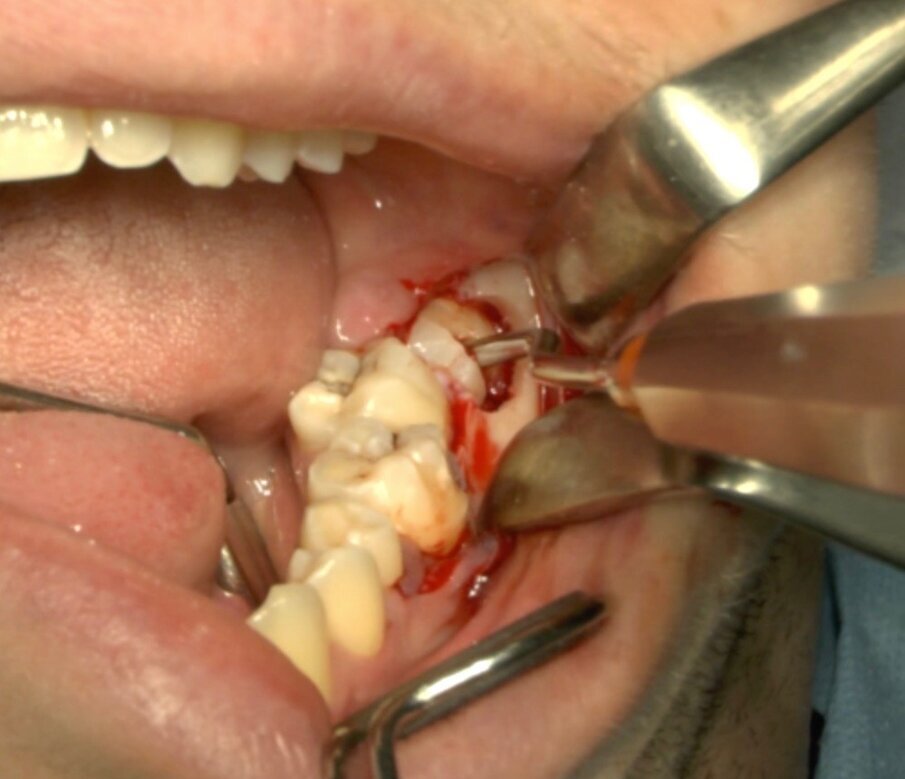

Protocollo standard

Ai pazienti viene prescritta una profilassi antibiotca con 2 gr di amoxicillina 1 h prima dell’intervento, si esegue quindi un anestesia di tipo tronculare con lidocaina senza vasocostrittore, poi infiltrazione di tipo plessica con adrenalina in corrispondenza del nervo buccinatore. Si scolpisce quindi un lembo a tutto spessore di tipo triangolare con incisione orizzontale alla base delle papille tra sesto e settimo ed incisione di scarico distale con andamento vestibolare (Figg. 1-4). Si procede con l’osteotomia che può essere eseguita con strumenti rotanti montati su manipolo retto oppure con terminale piezoelettrico con gli inserti dedicati. Qualora sia necessario si effettua l’odontotomia e la separazione radicolare con frese al carburo di tungsteno montate su turbina, quindi si esegue la lussazione e l’avulsione dell’elemento dentario. Si procede alla revisione della cavità alveolare con abbondante lavaggio con soluzione fisiologica, riempimento con collagene e sutura a punti staccati in seta 4/0. Il paziente viene dimesso con terapia analgesica ed antibiotica di supporto (Figg. 5-15).

Fig. 2_Situazione clinica iniziale 3.8 in inclusione orizzontale.

Fig. 4_Scheletrizzazione con visione della corone del 3.8.